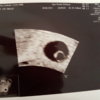

To moje wczorajsze usg na pierwszym zdjeciu widać fasolkę malusią A na ostatnim to cholerstwo.

A tu z krwiaczkiem po prawej stronie to podłużne

...........:::::::6tydz i 0dni:::::::::..........